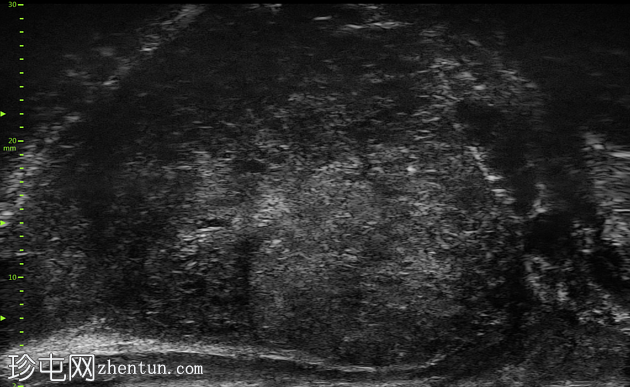

显微超声

1.png

超声

右侧旁矢状切面

尖部至中部

左侧旁矢状切面

尖部内侧

左侧尖部内侧呈“瑞士奶酪”样改变,无内部强回声或局灶性离散病灶。右侧尖部至中部可见一离散结节,内含混合回声病灶及不规则声影。

左侧尖部内侧的显微超声图像符合PRI-MUS 2级,提示前列腺癌风险较低。右侧尖部至中部的显微超声图像符合PRI-MUS 5级,提示前列腺癌风险极高。已对该区域进行靶向活检。

活检样本送至病理科进行检查,证实右侧前列腺为 4 级(Gleason 评分 4+4)腺癌。